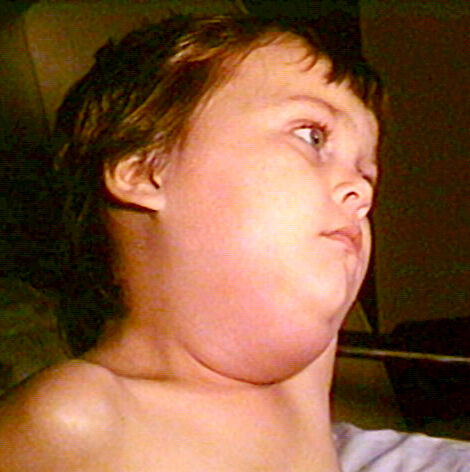

Mumps

Mumps can become inflamed and enlarged.

Symptoms of mumps include:

- Pain

- Bilateral swelling

- Fever

- Headache

- Muscle aches

- Exhaustion

- Appetite loss

Symptoms of mumps usually appear 10 days after being exposed to the virus.

Rarely, the mumps can lead to life-threatening side effects such as:

- Brain infection

- Pancreatic inflammation

- Liver disease

- Testicular damage

- Sterility

- Deafness